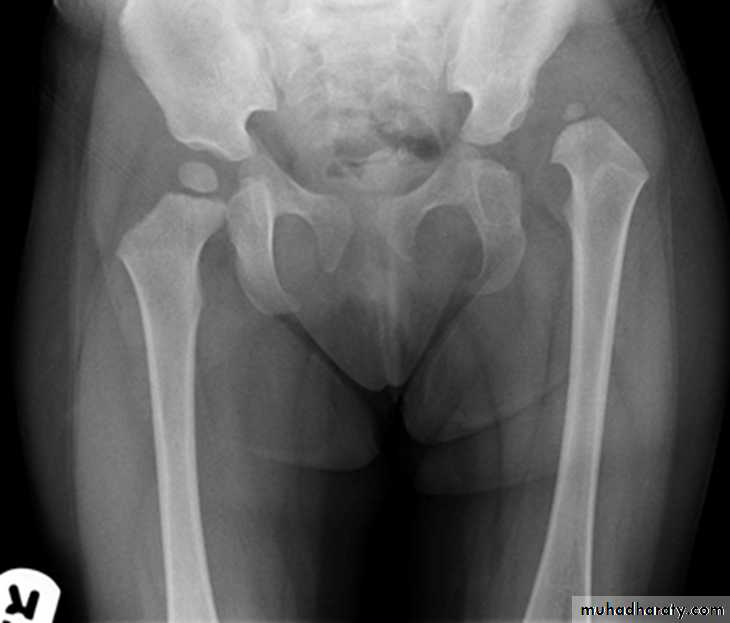

DEVELOPMENTAL DYSFLASIA OF HIP (CONGENITAL DISLOCATION OF THE HIP)

An abnormally lax joint capsule allows the femoral head to fall out of the acetabulum, leading to deformation.

CDH occurs most commonly (70%) in the left hip. Bilateral involvement is seen in 5%.

Radiographic features:

Plain film

At 3-6 months :

By doing special veiw (Von Rosen veiw )by abduction of the thigh 45 degree and internal rotation .

In DDH the lines that drown through the femura will meet in higher level than the normally should at lumbosacral joint .

6 months and later

* AP veiw ( femural epiphysis are visualized ):* Superolateral displacement of proximal femur (disturbed shenton’s line )

* Increase in acetabular angle

* Small capital femoral epiphysis

Femoral head is located lateral to Perkin's line

* Other features that are sometimes present

Abnormal sclerosis of the acetabulum

Shallow acetabulum

Formation of a false acetabulurn